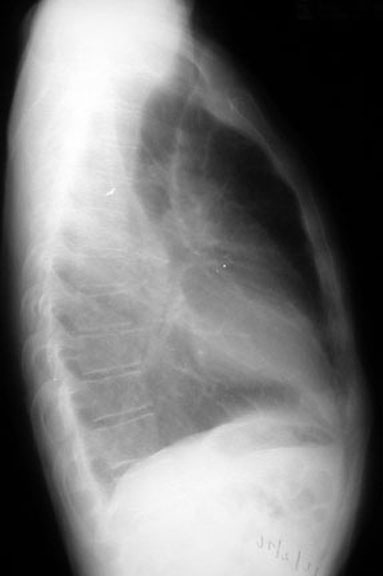

Pre-op lateral film

You can see both diaphragms